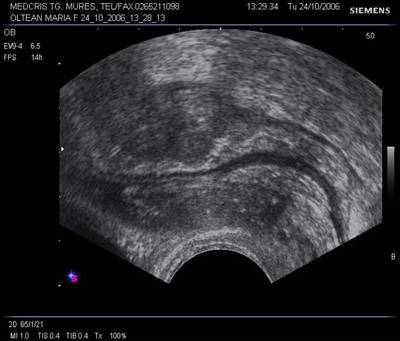

Fig. nr.403. Uter cu sac gestational, anterior vezica urinara in pozitia conventionala. Se remarca o zona anecogena in regiunea intervezicouterina ( colectie lichidiana postoperatie cezariana)